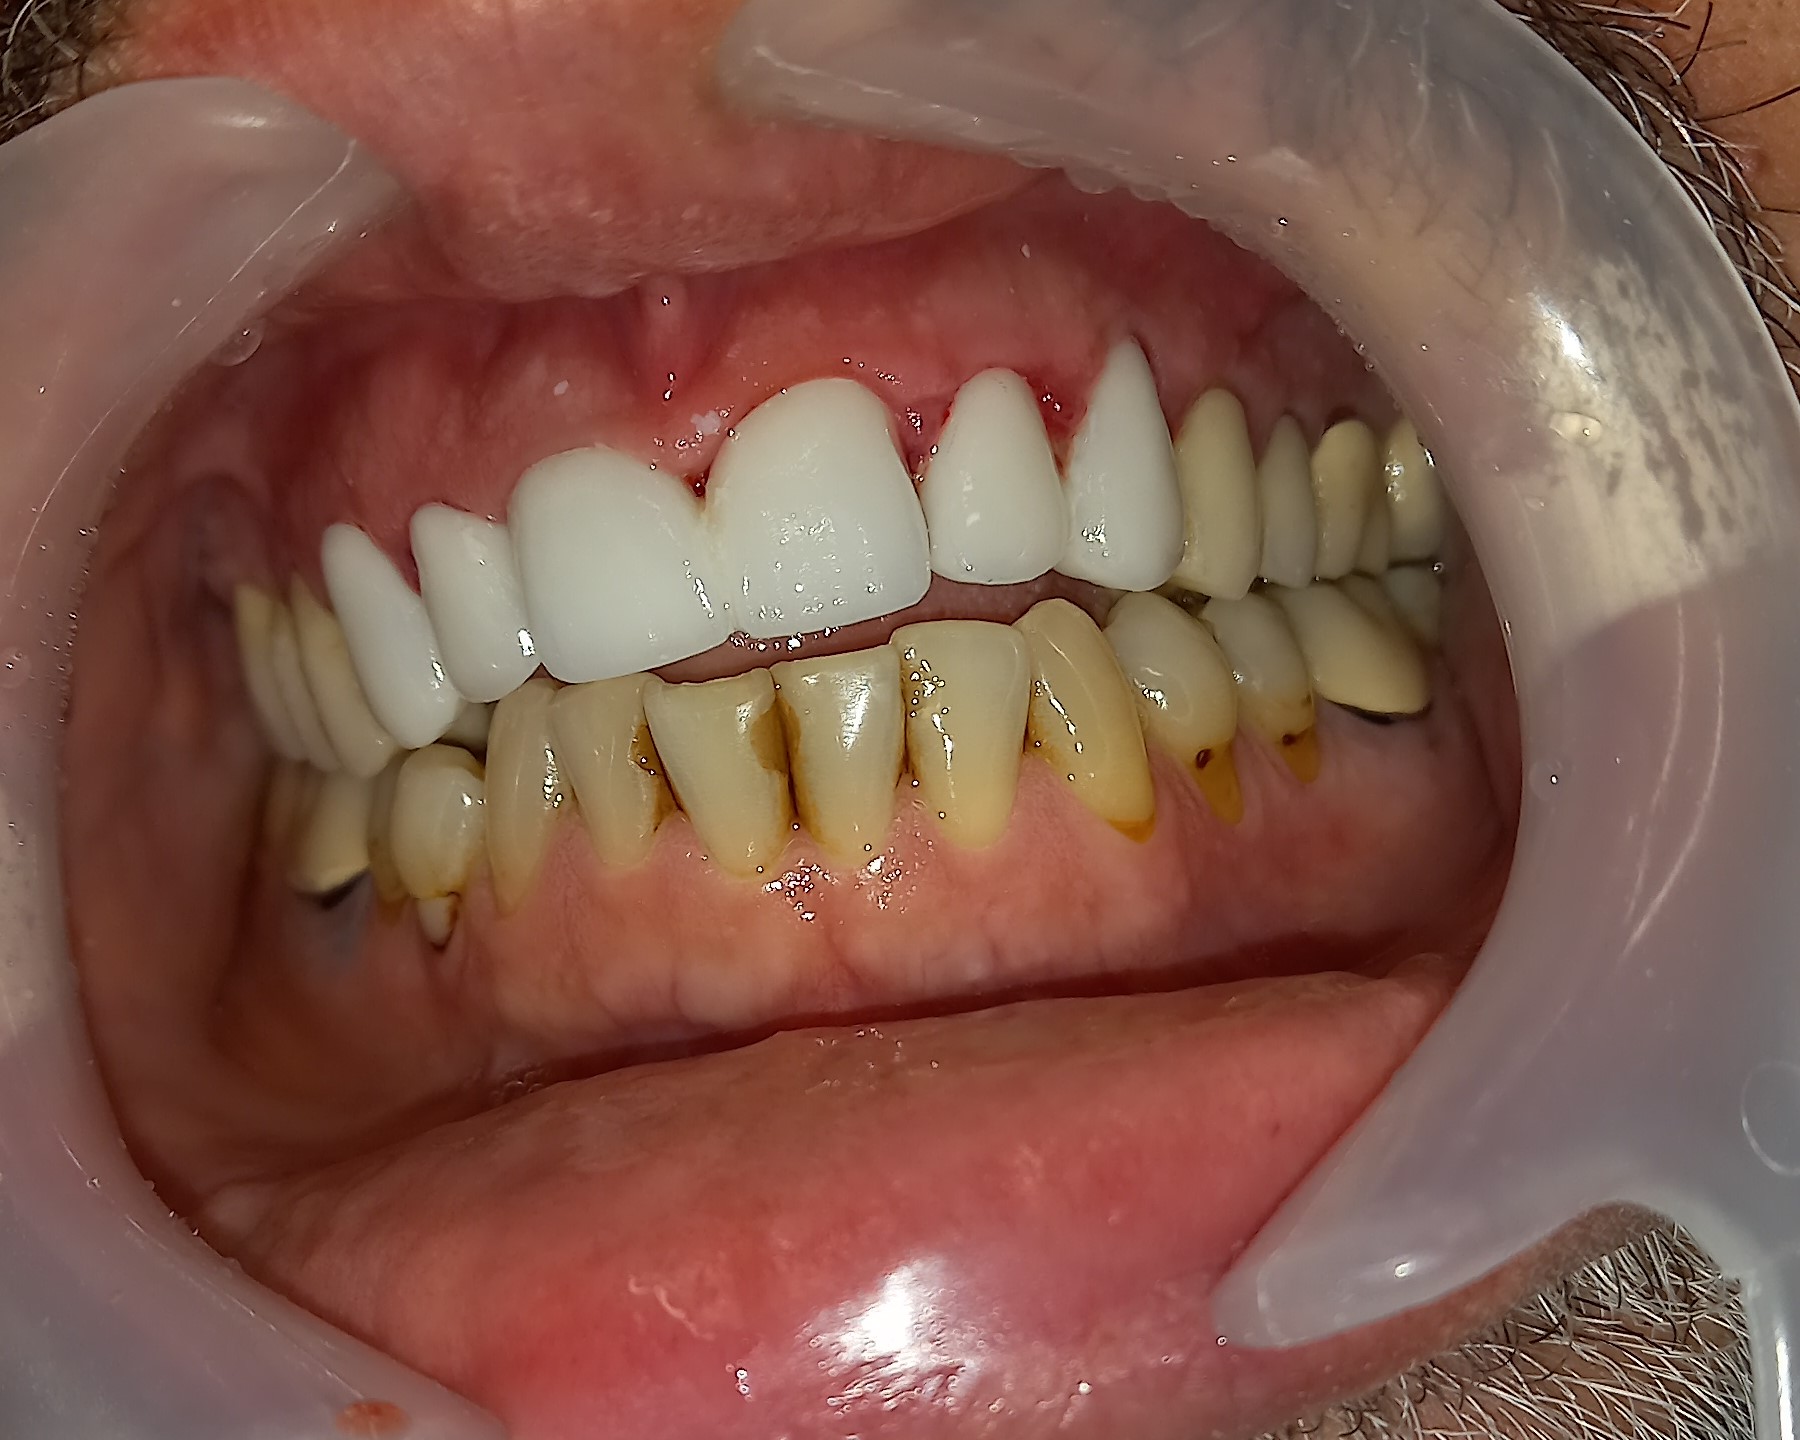

Ο ασθενής δεν είναι ευχαριστημένος με την αισθητική των 6 άνω πρόσθιων δοντιών. Επιπρόσθετα αυτά τα δόντια είχαν παλιές μεγάλες ανασυστάσεις, οι οποίες είχαν επανατερηδονιστεί. Για όλους τους ανωτέρους λόγους αποφασίστηκε, μετά από την απαραίτητη συζήτηση με τον ασθενή η αποκατάσταση των δοντιών με ολοκεραμικές θήκες. Τα δόντια τροχίστηκαν, αντικαταστάθηκαν οι παλιές εμφράξεις των δοντιών και στη συνέχεια λήφθηκαν αποτυπώματα, τα οποία στάλθηκαν στον οδοντοτεχνίτη. Σε όλη τη διάρκεια, που ο οδοντοτεχνίτης κατασκεύαζε τις νέες προσθετικές αποκαταστάσεις ο ασθενής φορούσε προσωρινές θήκες, οι οποίες είχαν ικανοποιητική αισθητική εμφάνιση.

Είναι σημαντικό να τονιστεί οτι ο ασθενής επιθυμούσε οι θήκες των 6 άνω πρόσθιων δοντιών να είναι αισθητά λευκές, παρόλο που διέφεραν χρωματικά από τα υπόλοιπα δόντια.

Ο ασθενής είναι ευχαριστημένος τόσο με την αισθητική όσο και με τη λειτουργία των νέων προσθετικών αποκαταστάσεων.

Αρχική κλινική εικόνα των 6 άνω πρόσθιων δοντιών

Προσωρινή αποκατάσταση των 6 άνω πρόσθιων δοντιών

Τελική κλινική εικόνα των 6 άνω πρόσθιων δοντιών